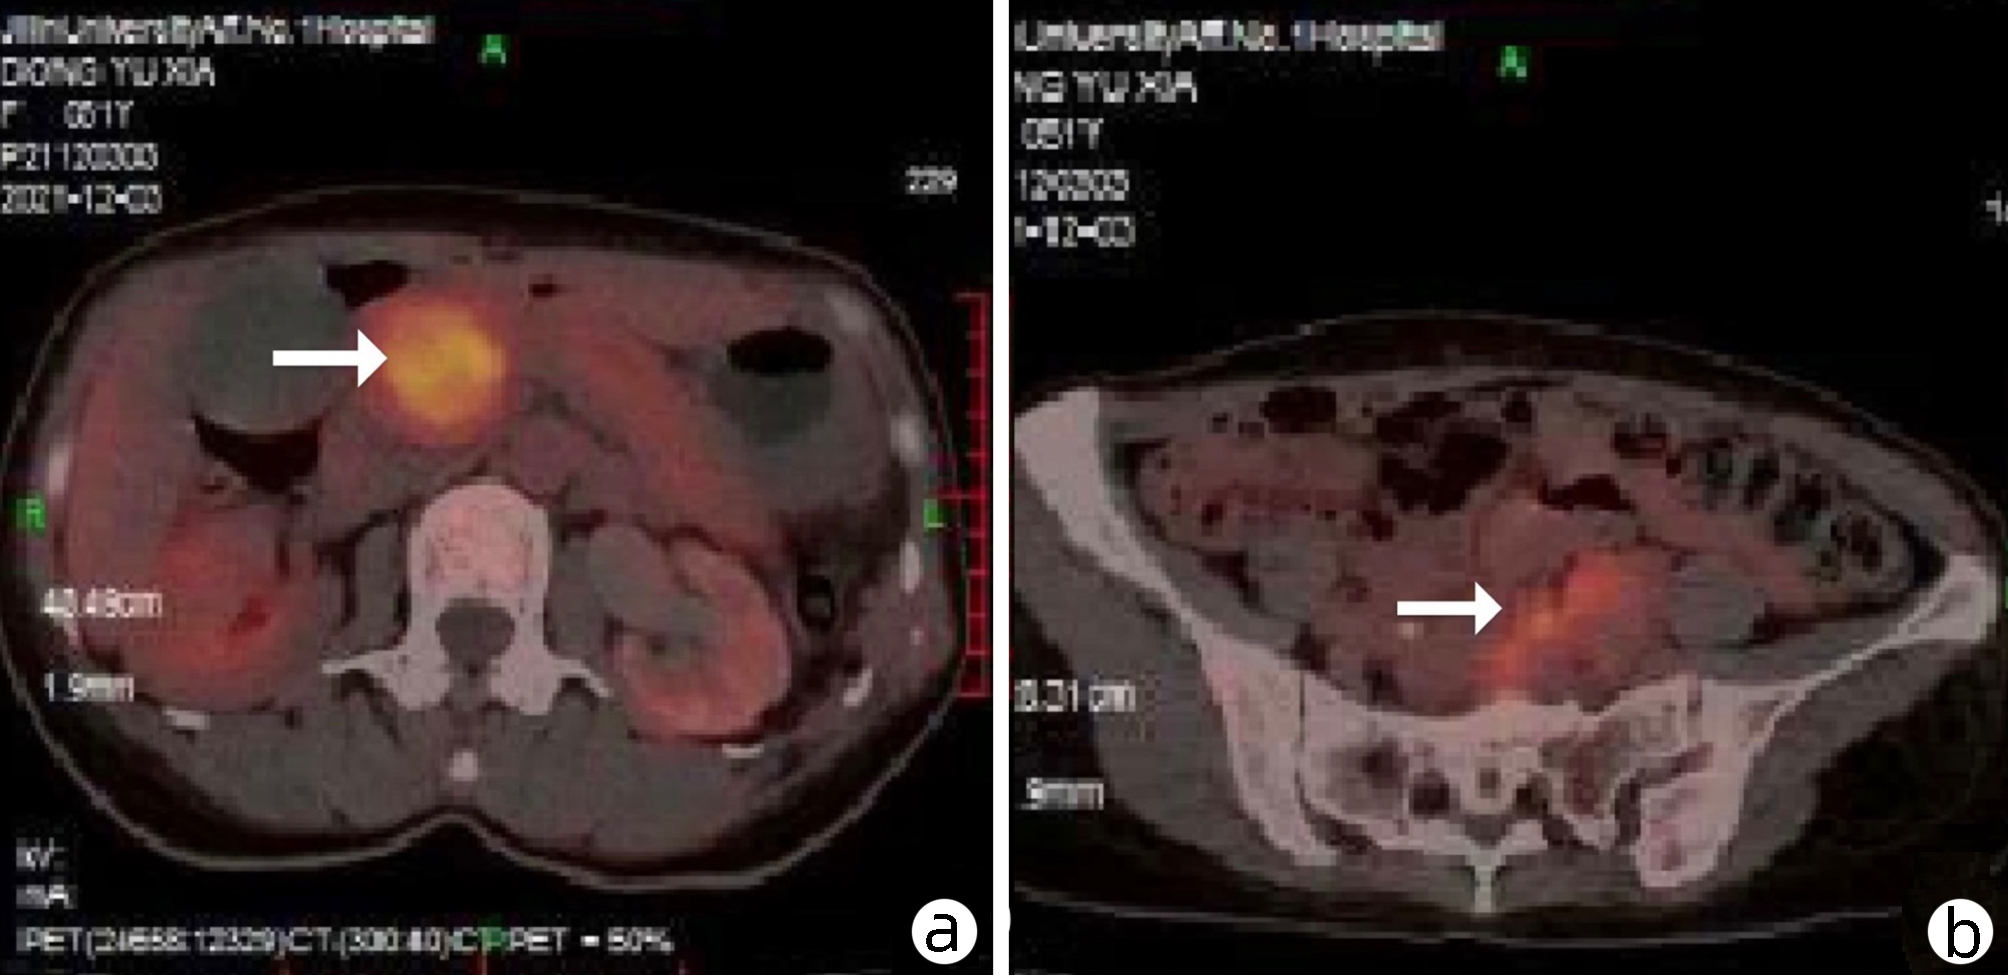

Value of 18F-FDG PET/CT, contrast-enhanced ultrasound, and their combined use in differential diagnosis of benign and malignant pancreatic lesions: A comparative study

Lichun ZHENG, Xiaoming ZHANG, Tianying YU, Jie LI, Xiaoqian DENG, Xiangliu OUYANG

2022, 38(12): 2774-2779. DOI: 10.3969/j.issn.1001-5256.2022.12.017

Abstract(2330) HTML (1630) PDF (3391KB)(64)

Abstract:

Objective  To assess the value of 18F-FDG PET/CT, contrast-enhanced ultrasound, and their combination in the differential diagnosis of benign and malignant pancreatic lesions.  Methods  A retrospective analysis was performed on patients with pancreatic lesions who underwent18F-FDG PET/CT and contrast-enhanced ultrasound who were admitted to Tangshan Gongren Hospital from January 2015 to December 2020. The imaging results were confirmed by pathology examination to evaluate diagnostic sensitivity, specificity, accuracy, positive and negative predictive value. The t-test was used for comparison of continuous data between two groups, and the chi-square test was used for comparison of categorical data between groups.  Results  There were 83 malignant lesions and 25 benign lesions in 108 patients. The sensitivity, specificity, accuracy, positive and negative predictive value were 86.75%, 80.00%, 85.19%, 93.51% and 64.52% for 18F-FDG PET/CT; and 69.88%, 76.00%, 71.30%, 90.63% and 43.18% for contrast-enhanced ultrasound, respectively. The two methods differed significantly in sensitivity and accuracy (all P < 0.05), but not in specificity, negative and positive predictive value (all P > 0.05). When combined with the contrast-enhanced ultrasound, 18F-FDG PET/CT had an increased sensitivity, specificity, accuracy, positive and negative predictive value of 90.36%, 84.00%, 88.89%, 94.94% and 72.41%, respectively, though this was not statistically significant due to the increased signal of blood supply in the lesions.  Conclusion  18F-FDG PET/CT has a better performance than contrast-enhanced ultrasound in the differential diagnosis of benign and malignant pancreatic lesions, and their combination can improve the diagnostic value.